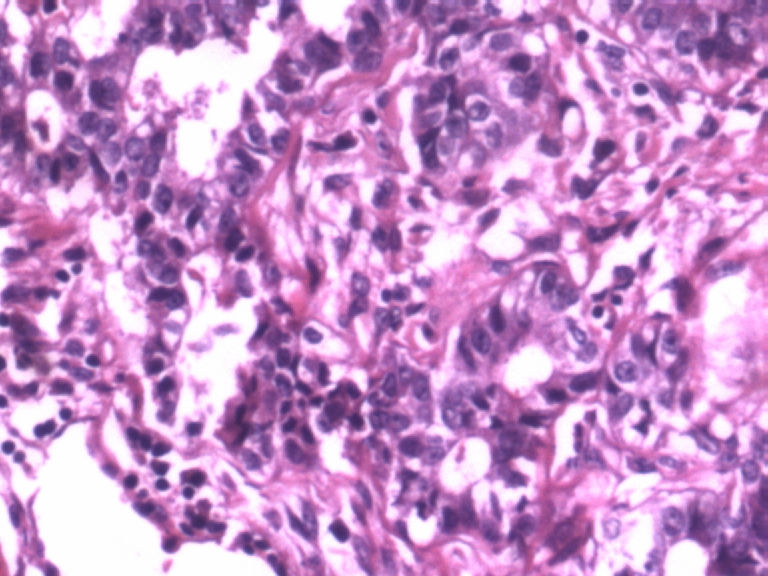

• 乳腺肿物图3

图3

患者,女,29岁,右侧乳腺肿物一个月。切面淡黄,均匀一致,质中。

标签:乳腺管状腺瘤

病变组织小叶结构未见,见管状、盲管状的腺管,周围似有空亮的肌上皮,腺上皮可见细小的核仁,染色质均细,导管上皮普通型增生。有包膜为盲管状腺瘤,则为腺病。

无则为腺病

结构有点乱,但是肌上皮还在,应该是良性范畴,最好标记一下。